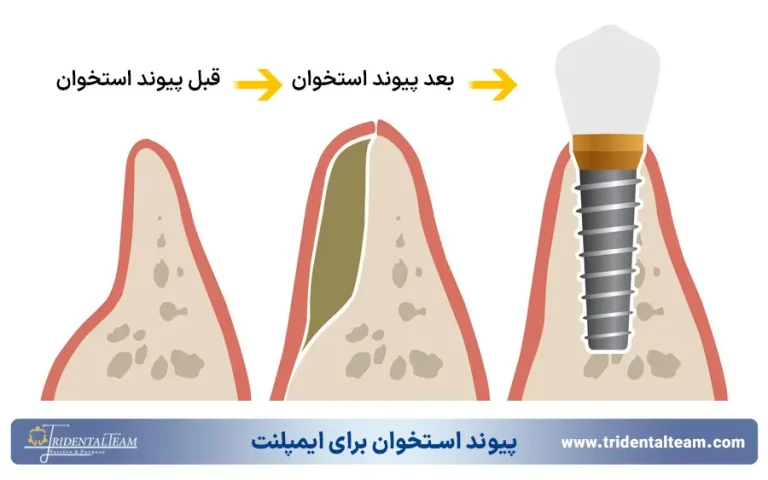

پیوند استخوان برای ایمپلنت دندان بدون درد

در برخی موارد، استخوان فک به دلیل گذشت زمان طولانی از کشیدن دندان یا تحلیل رفتن، تراکم کافی برای نگهداری ایمپلنت را ندارد. در چنین شرایطی، انجام پیوند استخوان برای ایمپلنت دندان ضروری است. این فرآیند اگرچه یک مرحله به درمان اضافه می کند، اما با تکنیک های مدرن می توان آن را نیز کاملا بدون درد انجام داد. استفاده از پودر استخوان های مصنوعی یا مشتق شده، نیاز به برداشتن استخوان از بدن خود بیمار را در بسیاری از موارد از بین برده است.

این جراحی معمولا تحت بی حسی موضعی کامل انجام می شود و بیمار در طول عمل هیچ دردی را حس نخواهد کرد. پس از جراحی نیز با تجویز داروهای مسکن مناسب، دوره نقاهت به راحتی سپری خواهد شد. انجام صحیح این مرحله، پایه ای محکم برای موفقیت ایمپلنت ایجاد کرده و از بروز مشکلاتی مانند عفونت ایمپلنت دندان در آینده جلوگیری می کند.